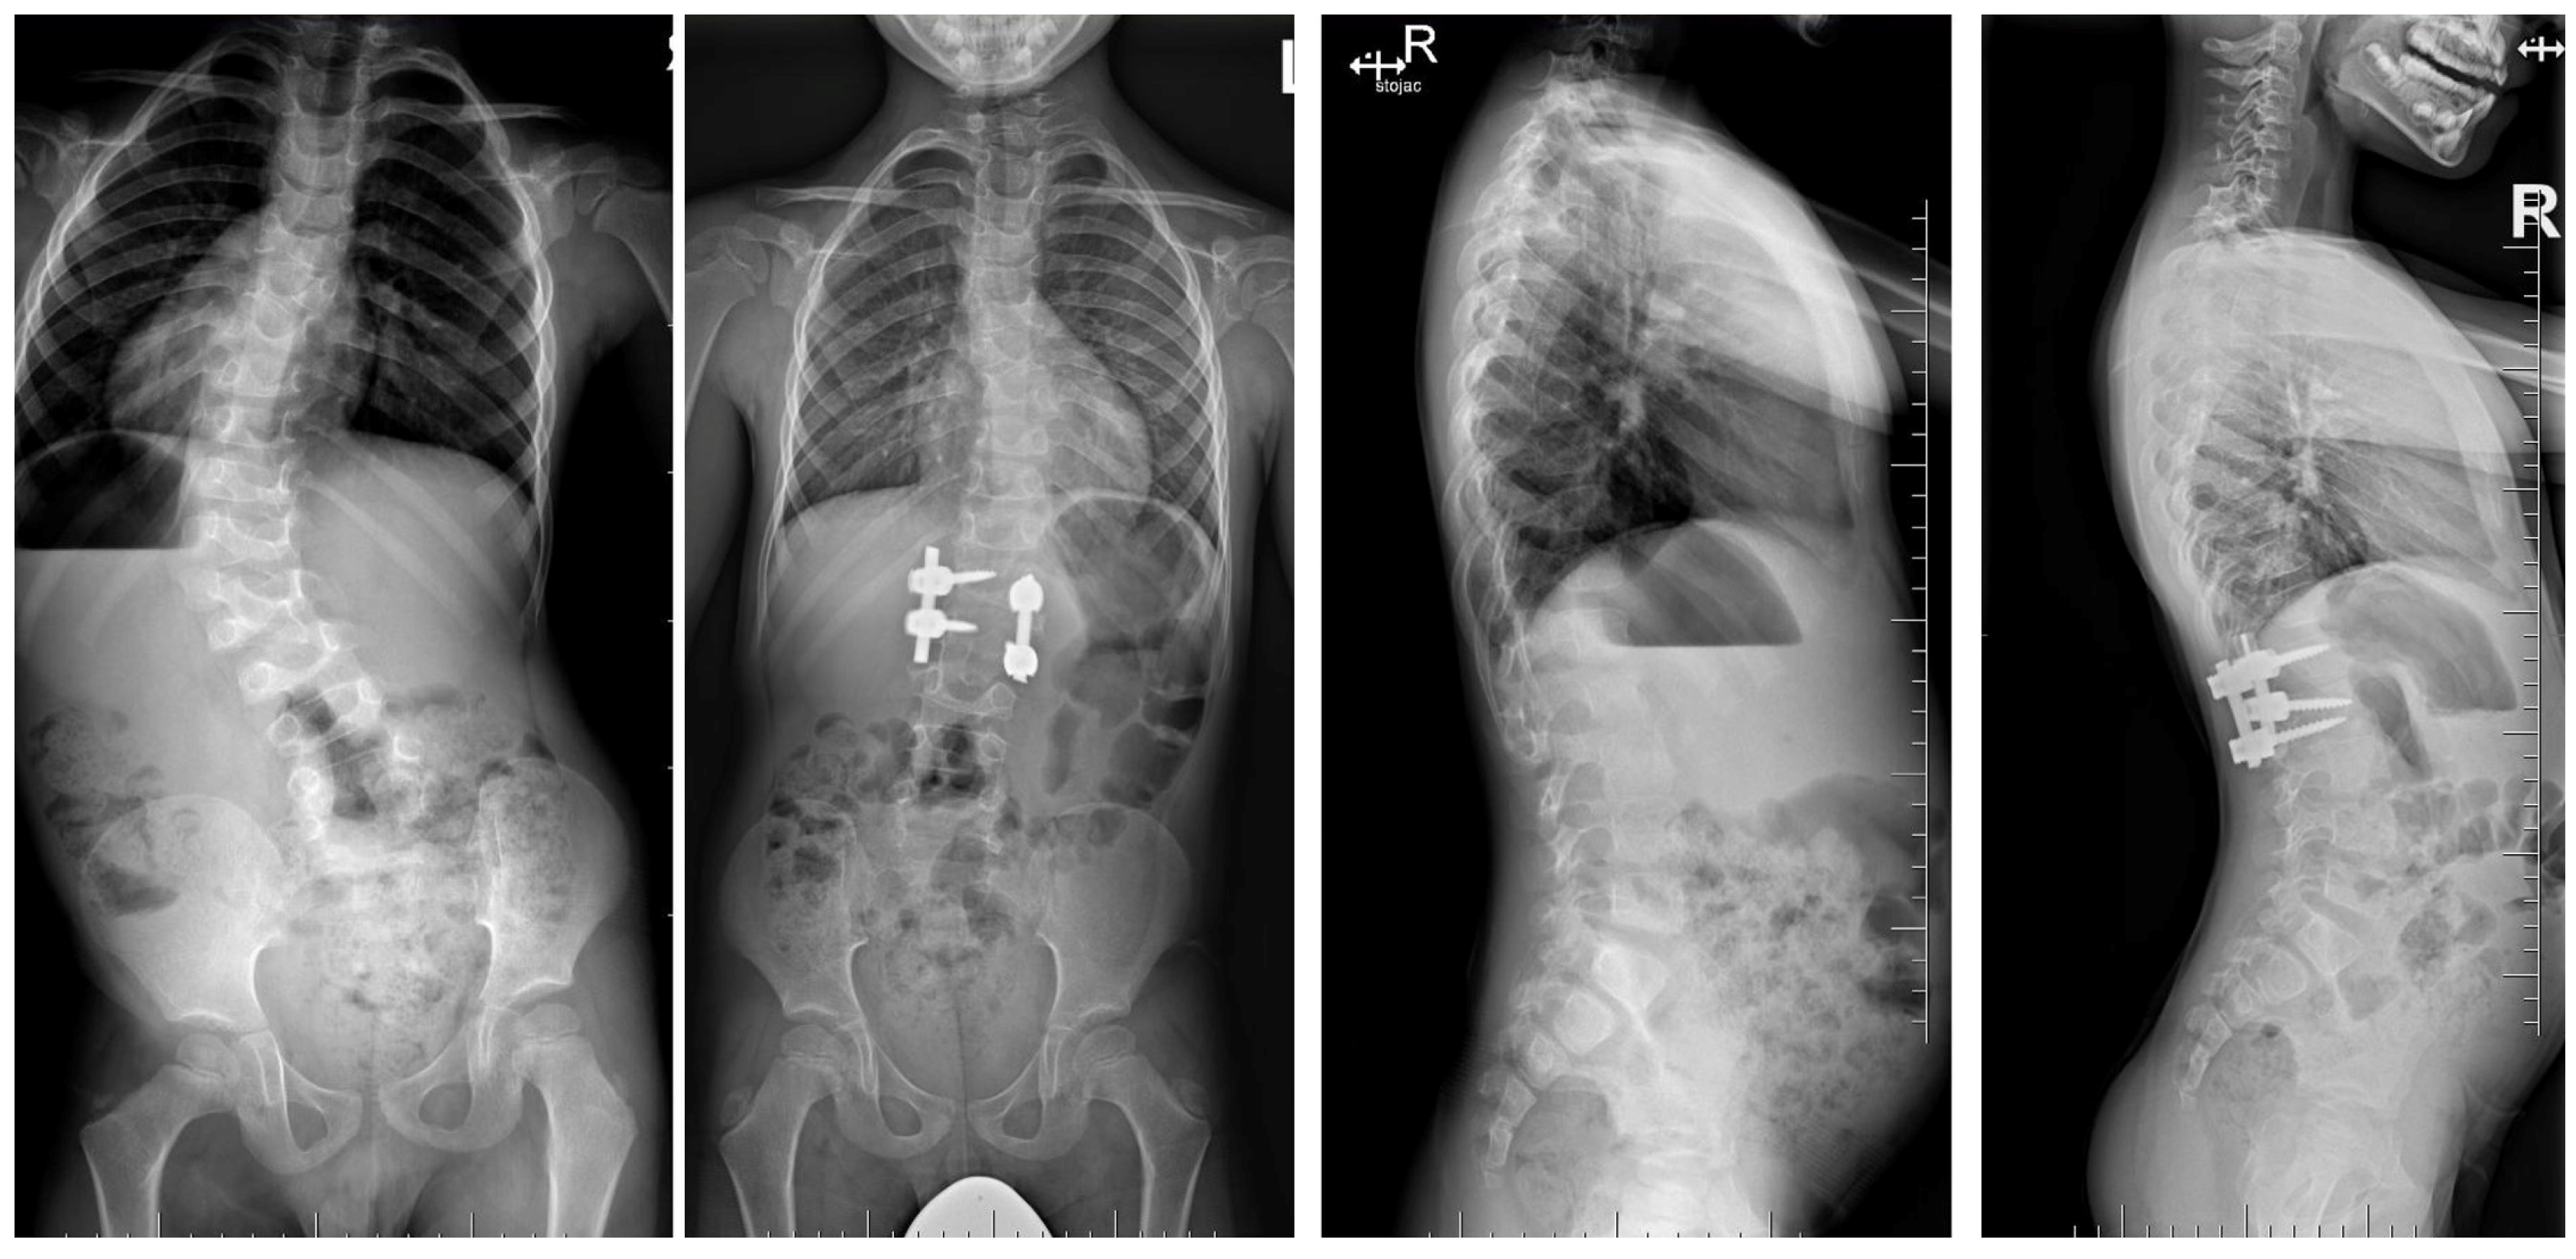

6.1. Radiographic Evaluation

6.2. Advanced Imaging Modalities

7.3. Surgical Techniques

7.3.3. Hemivertebrectomy

7.3.4. Growing Rod Systems